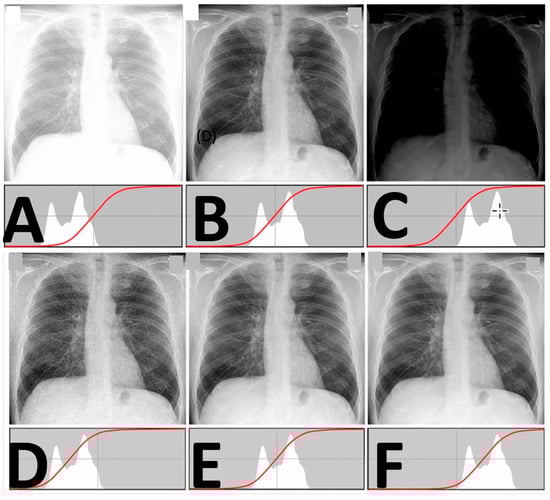

- In this calibration tests, the pediatric phantom was used in over-and-under-exposure settings and the images were evaluated by a certified radiologist to systematize the correspondence between the tests’ gray-level histogram (calculated using ImageJ -ImageJ NIH, Version 1.54p 2024) and the diagnostic quality of the image.